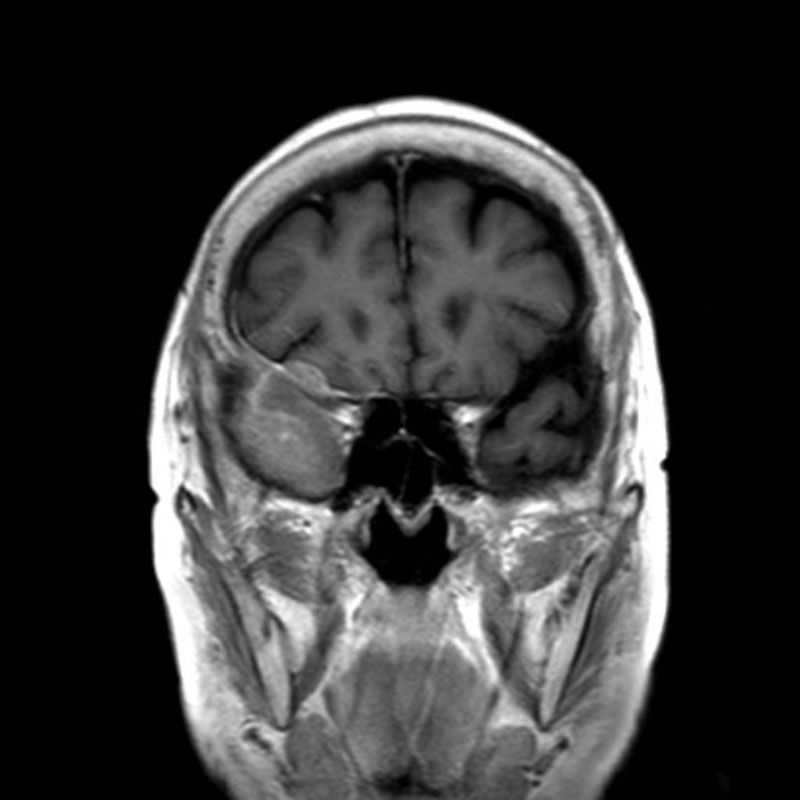

No.’25_113 手術前1

No.’25_113 手術前2